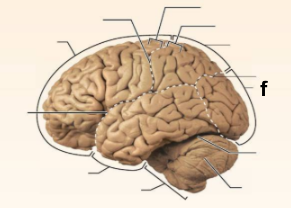

Identify the structure labeled “a” in the image.

Brain Stem

Identify the structure labeled “b” in the image.

Central culcus

Identify the structure labeled “c” in the image.

Cerebellum

Identify the structure labeled “d” in the image.

Frontal lobe

Identify the structure labeled “e” in the image.

Lateral sulcus

Identify the structure labeled “f” in the image.

Occipital lobe

Identify the structure labeled “g” in the image.

Parietal lobe

Identify the structure labeled “h” in the image.

Parieto-occipital sulcus

Identify the structure labeled “i” in the image.

Postcentral gyrus

Identify the structure labeled “j” in the image.

Precentral gyrus

Identify the structure labeled “k” in the image.

Temporal lobe

Identify the structure labeled “l” in the image.

Transverse cerebral fissure